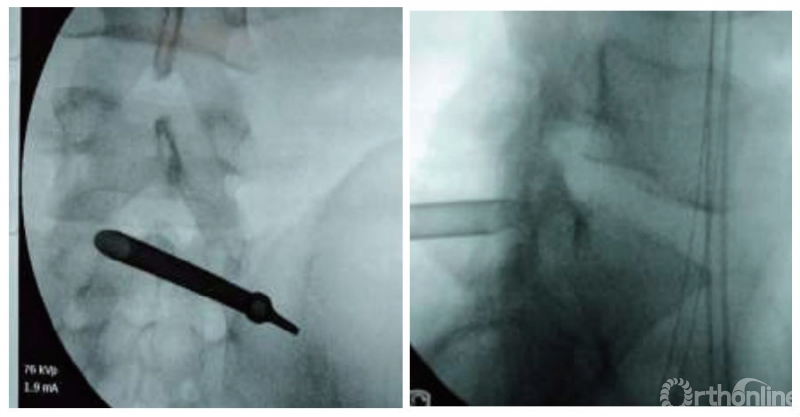

(2)穿刺、放置工作套筒:常规消毒铺巾,沿穿刺点经L5/S1关节突关节内侧抵达椎间盘突出位点。拔出穿刺针针芯插入导针,拔出穿刺针,以导针为中心用尖刀纵向刺入皮肤达深筋膜,确保深筋膜被切开,切口长约0.8cm,以扩张器沿导针扩张分离至黄韧带表层,沿扩张器置入工作套管(图3),连接光源及视频成像系统。

图注:B组为伴有高髂嵴的L5/S1椎间盘突出症患者,采用后方入路经皮椎板间椎间孔镜下椎间盘切除治疗

图3|B组正、侧位透视显示后方经皮椎板间入路椎间孔镜下椎间盘切除术工作套筒的位置